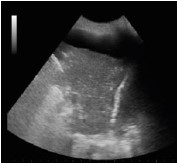

Paciente de 70 anos do sexo masculino dá entrada no Pronto-Socorro após iniciar quadro de dispneia em churrasco, há cerca de 1 hora.

Relata ser hipertenso e ter insuficiência cardíaca. Ao exame clínico, dispneico, FR 30, SatO2 77% em ar ambiente, FC 110 e PA 190x120, com ausculta pulmonar com estertores finos até ápices.

Assinale a opção que apresenta a imagem de ultrassonografia pulmonar compatível com a descrição do quadro acima.